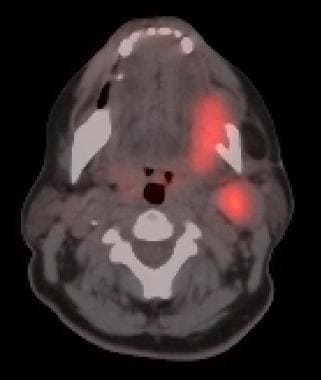

PET-CT combines the functional information obtained from positron emission tomography (PET) with the anatomical details provided by computed tomography (CT). PET utilizes a radioactive tracer, typically fluorodeoxyglucose (FDG), which is taken up by metabolically active cells, such as cancer cells. By detecting the concentration of FDG, PET can highlight areas of increased metabolic activity, indicating the presence of tumors or areas with potential malignancy. The addition of CT imaging allows for precise anatomical localization of these areas, providing a comprehensive view of the tumor and its surrounding structures.

In PET imaging, the standardized uptake value (SUV) is a quantitative measure used to assess the level of FDG uptake within a tumor or lesion. SUV measurement provides valuable information about the metabolic activity of the tumor and helps in characterizing its aggressiveness. Higher SUV values often indicate a higher metabolic rate and increased tumor activity. The SUV measurement serves as an important parameter in cancer assessment and can assist in several aspects, including staging, treatment response evaluation, and predicting patient outcomes.

In head and neck malignancy, SUV values play a significant role in determining the extent and behavior of the tumor. Different malignancies can exhibit varying SUV values depending on their characteristics. For example, a higher SUV value in a head and neck tumor may suggest a more aggressive tumor phenotype and a higher likelihood of metastasis. On the other hand, a lower SUV value may indicate a less metabolically active tumor with a potentially better prognosis.

2. Detection of Occult Primary Tumors: In some cases, patients may present with cervical lymphadenopathy without an identifiable primary tumor. PET-CT scan, along with SUV measurement, can help locate the occult primary tumor by detecting areas of increased metabolic activity, potentially guiding targeted biopsies and treatment decisions.